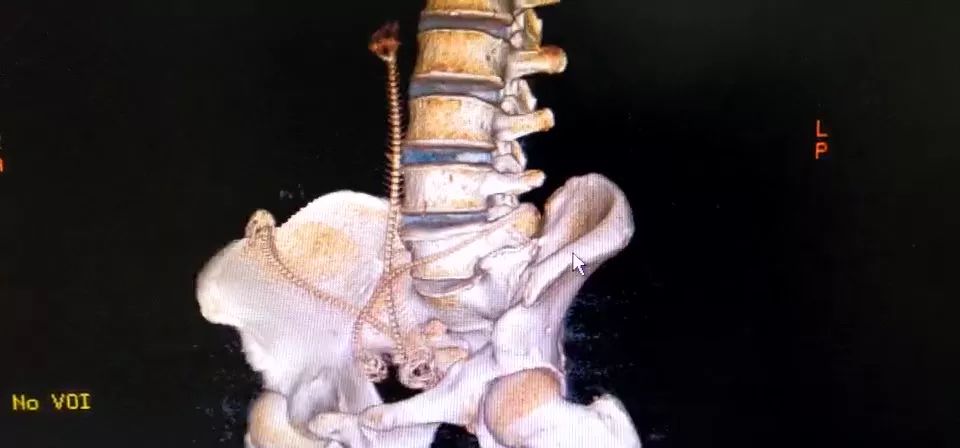

CT三维重建下三条泥鳅的骨骼清晰可见

占据整个下腹部和盆腔......

2月10日那天我看的急诊,事情的经过是这样的,我是他的首诊大夫,一开始急诊打电话急会诊说是吃泥鳅吃坏了肚子,我觉得这也没啥,然后让他做腹部CT。后来看到他的CT赫然三条鱼骨头。我一看CT很吃惊,难道是生吃的?

去一楼急诊问患者本人,当时我听他说了事实,是下面塞进去的真把我吓一跳。他第一句话就是说,听信网上前列腺偏方把他害惨了,让我救救他赶紧手术,问我有没有穿孔,当时只有一个小时,还早,摸着板状腹很硬。他意识还有,后来就慢慢感染中毒休克了。后来术中发现乙状结肠穿孔,三条鱼都到了腹腔里,有一条还往回盲部钻,不过取出来应该都是死的了。